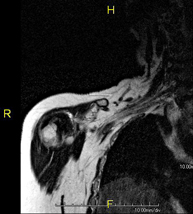

- TMJ MRI (Temporomandibular Joint Magnetic Resonance Imaging)

This non-invasive diagnostic procedure uses an electromagnetic field and radio waves (from a transmitter and receiver) to acquire high-definition anatomical images of the jaw joint. It is a radiation-free procedure. A functional study of the TMJ is performed during the different phases of mouth opening and closing. Indicated for: pain, joint blockage and noises during chewing.